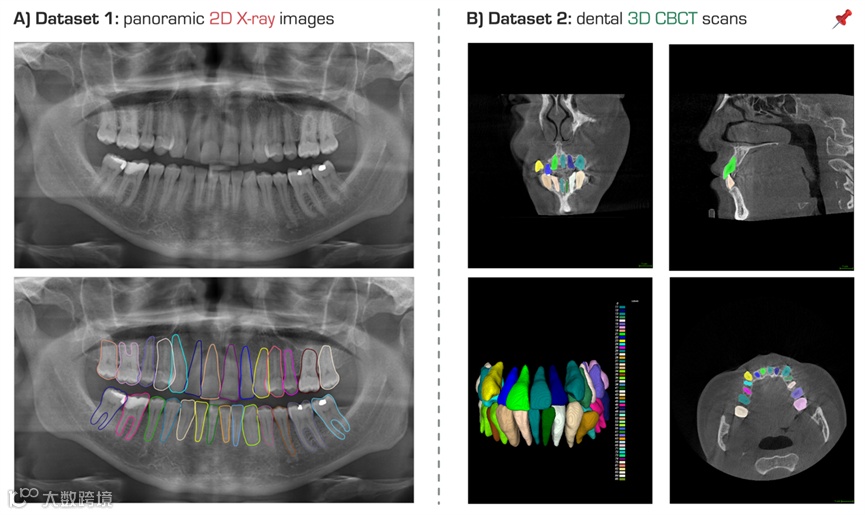

计算机辅助诊断工具在现代牙科中受到越来越多的关注,特别是用于治疗计划或预后评估。其中,2D全景X射线图像是牙医确定儿童隐形龋齿、受影响牙齿和多余牙齿的有效方法。此外,3D牙科锥束计算机断层扫描(CBCT)检查因其低射线剂量和可视化三维结构的能力而被广泛用于正畸和牙髓学。然而,从全景X射线图像或CBCT扫描中定位识别牙齿,并进一步手动分割牙齿仍然是一件费时费力的工作。因此,我们通常无法获得大量有标注病例,这限制了深度学习算法在牙齿实例分割和牙科疾病分析的发展。半监督学习作为一种解决方案可以从未标注的数据中探索有用的信息。因此,我们举办Semi-TeethSeg MICCAI 2024挑战赛,致力于开发高效的半监督学习方法,从全景X射线图像或CBCT扫描中自动地分割不同的牙齿实例。通过这一挑战赛,我们希望为医学图像分析领域设立一个更加全面的多实例分割基准,并加速临床实践中牙科疾病诊断工具的开发和应用,以进一步改善对牙科的诊疗管理流程。

1)任务1:全景X射线图像牙齿实例分割,jpg格式,共2450例:

2)任务2:牙科CBCT影像牙齿实例分割,nii.gz格式,共400例: